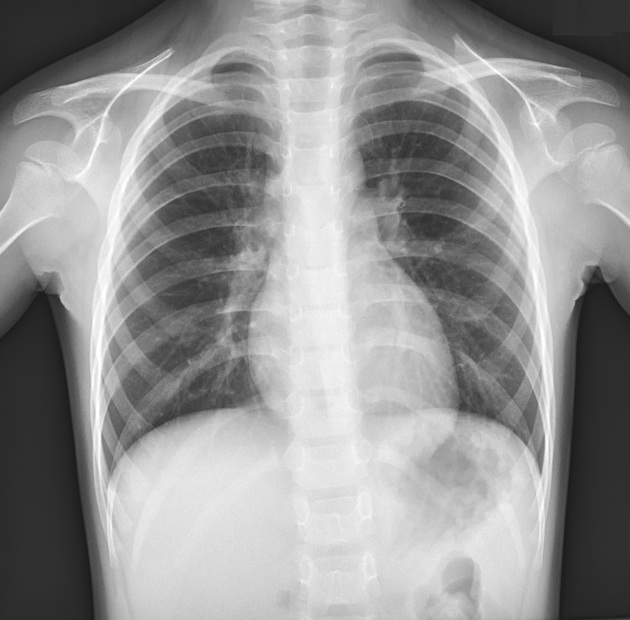

Normal Infant Chest Xray

Xray showing the thorax preoperatively with obvious signs of a funnel Funnel Chest 1 Year Old Pectus excavatum, also known as sunken chest or funnel chest, is the most frequent congenital anomaly of the chest wall, occurring in 1 in 400 births, and is found in 2.6 percent of children. This causes a depression in. The two most common types of chest wall deformities include: Learn about pectus excavatum, a condition where the breastbone presses inwards. Funnel Chest 1 Year Old.

Xray showing the thorax preoperatively with obvious signs of a funnel Funnel Chest 1 Year Old Also called a funnel chest, kids with this condition have an indented or sunken sternum (center of the. Pectus excavatum, also known as concave chest or funnel chest, is a chest wall deformity in which a child’s breastbone (sternum) and some of the ribs grow inward. Pectus excavatum is a chest wall disorder that makes the ribs and sternum grow. Funnel Chest 1 Year Old.